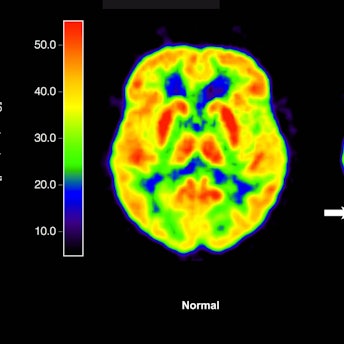

Leqembi, dem ersten von der FDA zugelassenen Medikament gegen Alzheimer, das Beta-Amyloid-Ablagerungen im Gehirn abbaut.

Der von den internationalen Unternehmen Eisai und Biogen entwickelte Antikörper heftet sich an die Eiweißablagerungen im Gehirn, die als Auslöser für die Entstehung von Alzheimer gelten, und regt das Immunsystem dazu an, diese Ablagerungen abzubauen.